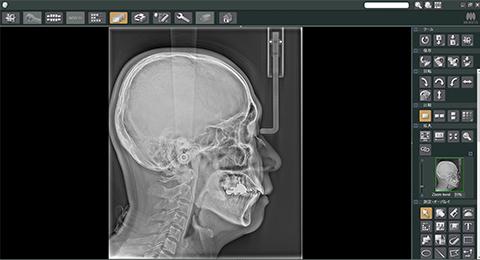

矯正治療における抜歯基準は、長年セファロ分析を中心に語られてきました。

中切歯の角度がどうであるか、上下顎の前後関係がどうであるか、それを改善するためにスペースが必要だから抜歯を行う、という考え方です。

理由は明確で、実際の歯列は側貌だけでは成立していないからです。

セファロ分析の中で、私が特に重視しているポイントがキーリッジです。

上顎第一大臼歯の近心頬側根がキーリッジ直下に位置しているかどうかは、歯列全体の安定性を考える上で極めて重要です。

これは単なる前歯の角度評価では見えてこない要素であり、実際の臨床判断に直結します。